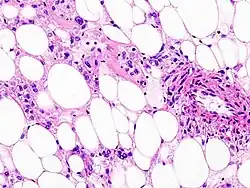

![]() Obraz histologiczny naczyniakomięśniakotłuszczaka. Preparat z nefrektomii | |

Makroskopowo guz przypomina raka nerki, ma żółtą barwę i znajdują się w nim ciemne ogniska krwotoczne. Zgodnie z nazwą, guz zawiera tkankę tłuszczową, mięśnie gładkie i naczynia krwionośne. Naczynia są grubościenne i często tętniakowato poszerzone. W obrazie histologicznym widać przemieszane komórki tkanki tłuszczowej, włókna mięśni gładkich i naczynia; miocyty mogą wykazywać polimorfizm, a niekiedy obecne są w nich figury podziałów mitotycznych. Guz daje dodatnią reakcję immunohistochemiczną z przeciwciałami HMB-45, co ułatwia różnicowanie go z rakiem nerki albo onkocytomą.